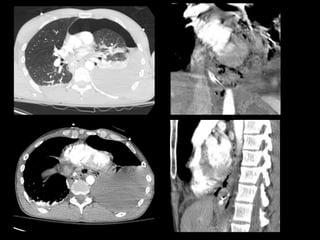

This document describes four patient cases seen by different doctors, including a 72-year-old female with abdominal pain, a 42-year-old female with abdominal pain and bloody diarrhea, a 37-year-old male with chest pain and vomiting of digested blood, and a 67-year-old male with an abnormal heart ultrasound.